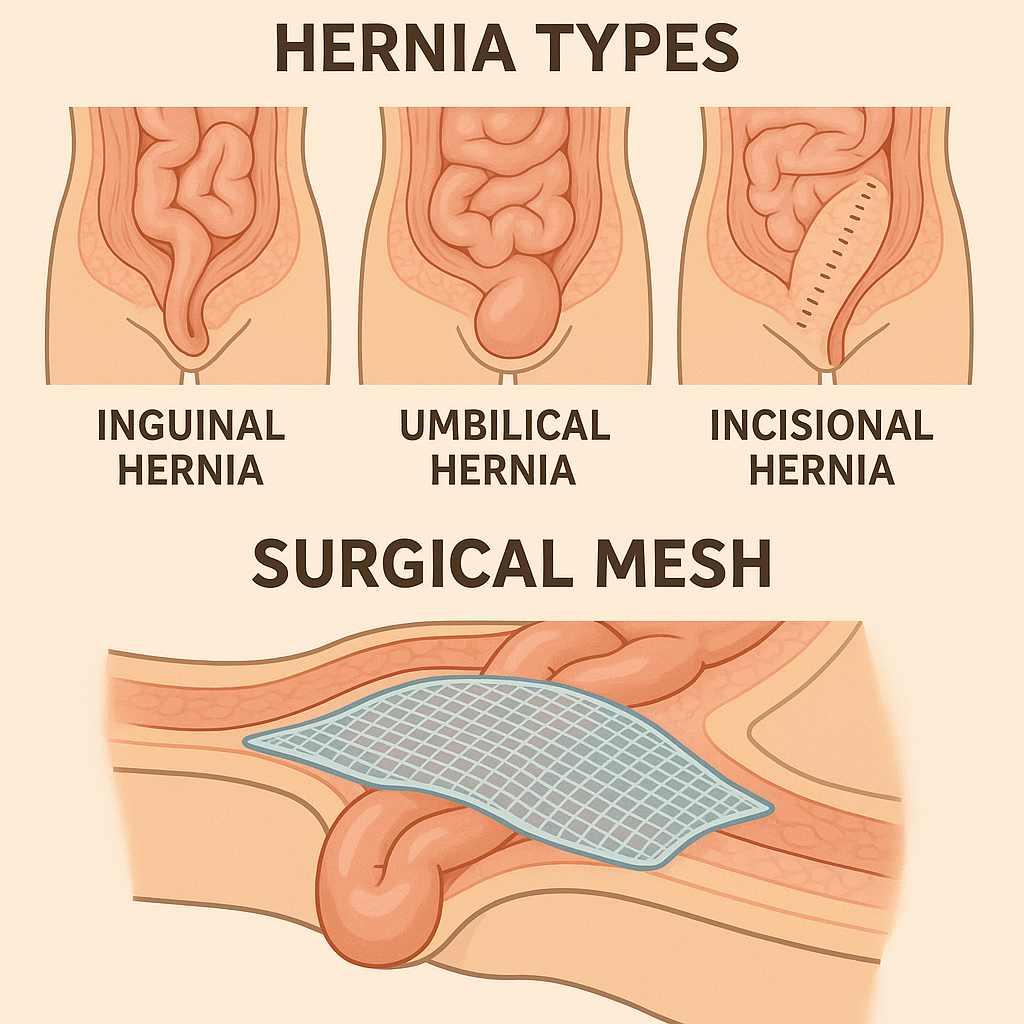

General & Laparoscopic Surgery